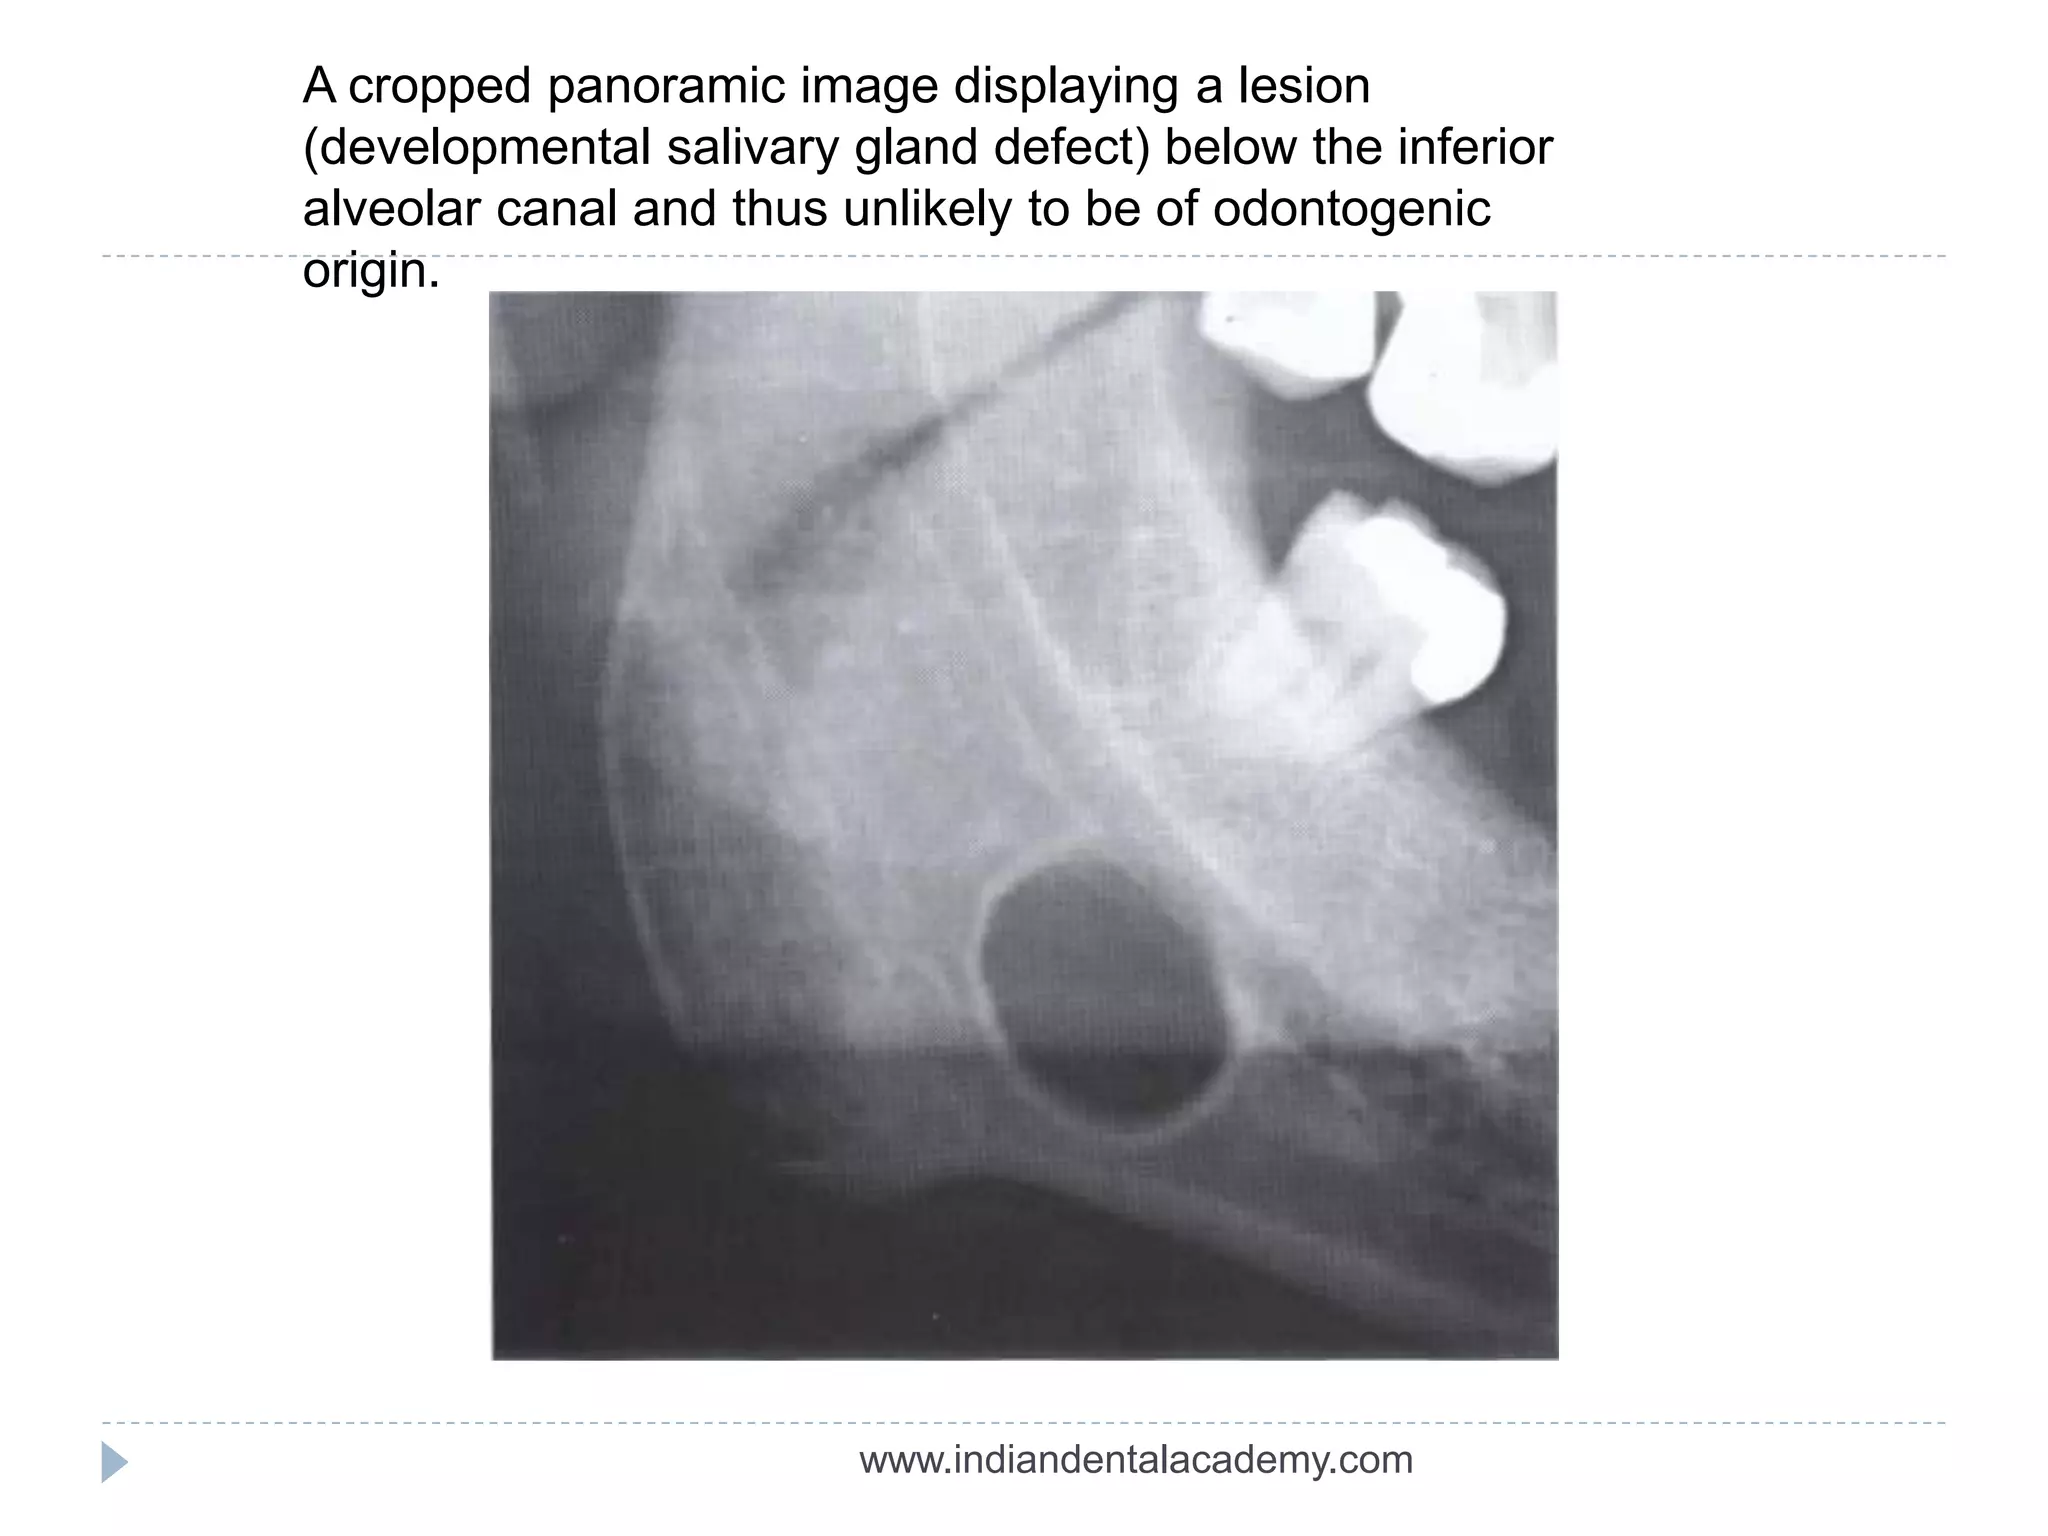

A cropped panoramic image displaying a lesion

(developmental salivary gland defect) below the inferior

alveolar canal and thus unlikely to be of odontogenic

origin.

A cropped panoramicimage displaying a lesion (developmental salivary gland defect) below the inferior alveolar canal and thus unlikely to be of odontogenic origin. www.indiandentalacademy.com